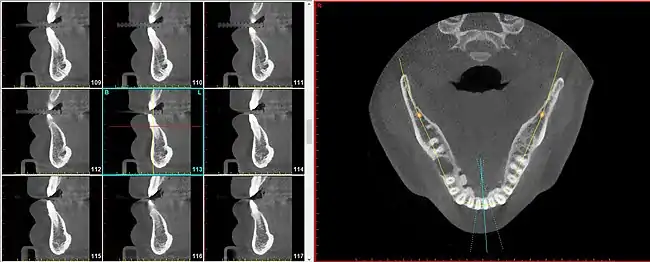

On the right, an axial slice through a human mandible as viewed on a CBCT. The three blue lines in the lower portion of the radiograph each portray radial slices. On the left, nine radial slices, three of which are represented by the blue lines on the right side.

A radial plane is an anatomical plane that is used to describe a virtual slice along a radius of a somewhat cylindrical shaped body part.[1] The radial planes need not be perfectly drawn to overlap on an exact intersection point, particularly when the body part being sectioned is not a perfect cylinder, such as in the case of the maxilla and mandible.

The radial plane can be useful because certain anatomical elements repeat in a circumferential manner (such as around the curvature of the dental arch (i.e. the jaw) and to speak of these entities using parallel planes becomes cumbersome and inaccurate.

For instance, the segment of bone on the outer circumference of each individual tooth is referred to as the facial plate of bone. Because the facial plate of bone is anterior to the incisors (in the front of the mouth) but lateral to the premolars and molars (in the back of the mouth), to visualize the facial plate of bone on various teeth will require sagittal slices for the former but coronal slices for the latter. To achieve greater uniformity and diminished confusion, simply speaking of radial slices provides a satisfactory solution for all teeth in both (upper and lower) arches.